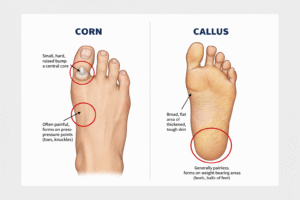

How to Safely Remove Calluses When You Have Diabetes (Without Risking Your Health) If you have diabetes and notice thickened,...

What Are Corns and Calluses? Let’s be honest—most people don’t think twice about thickened skin on their feet until it...